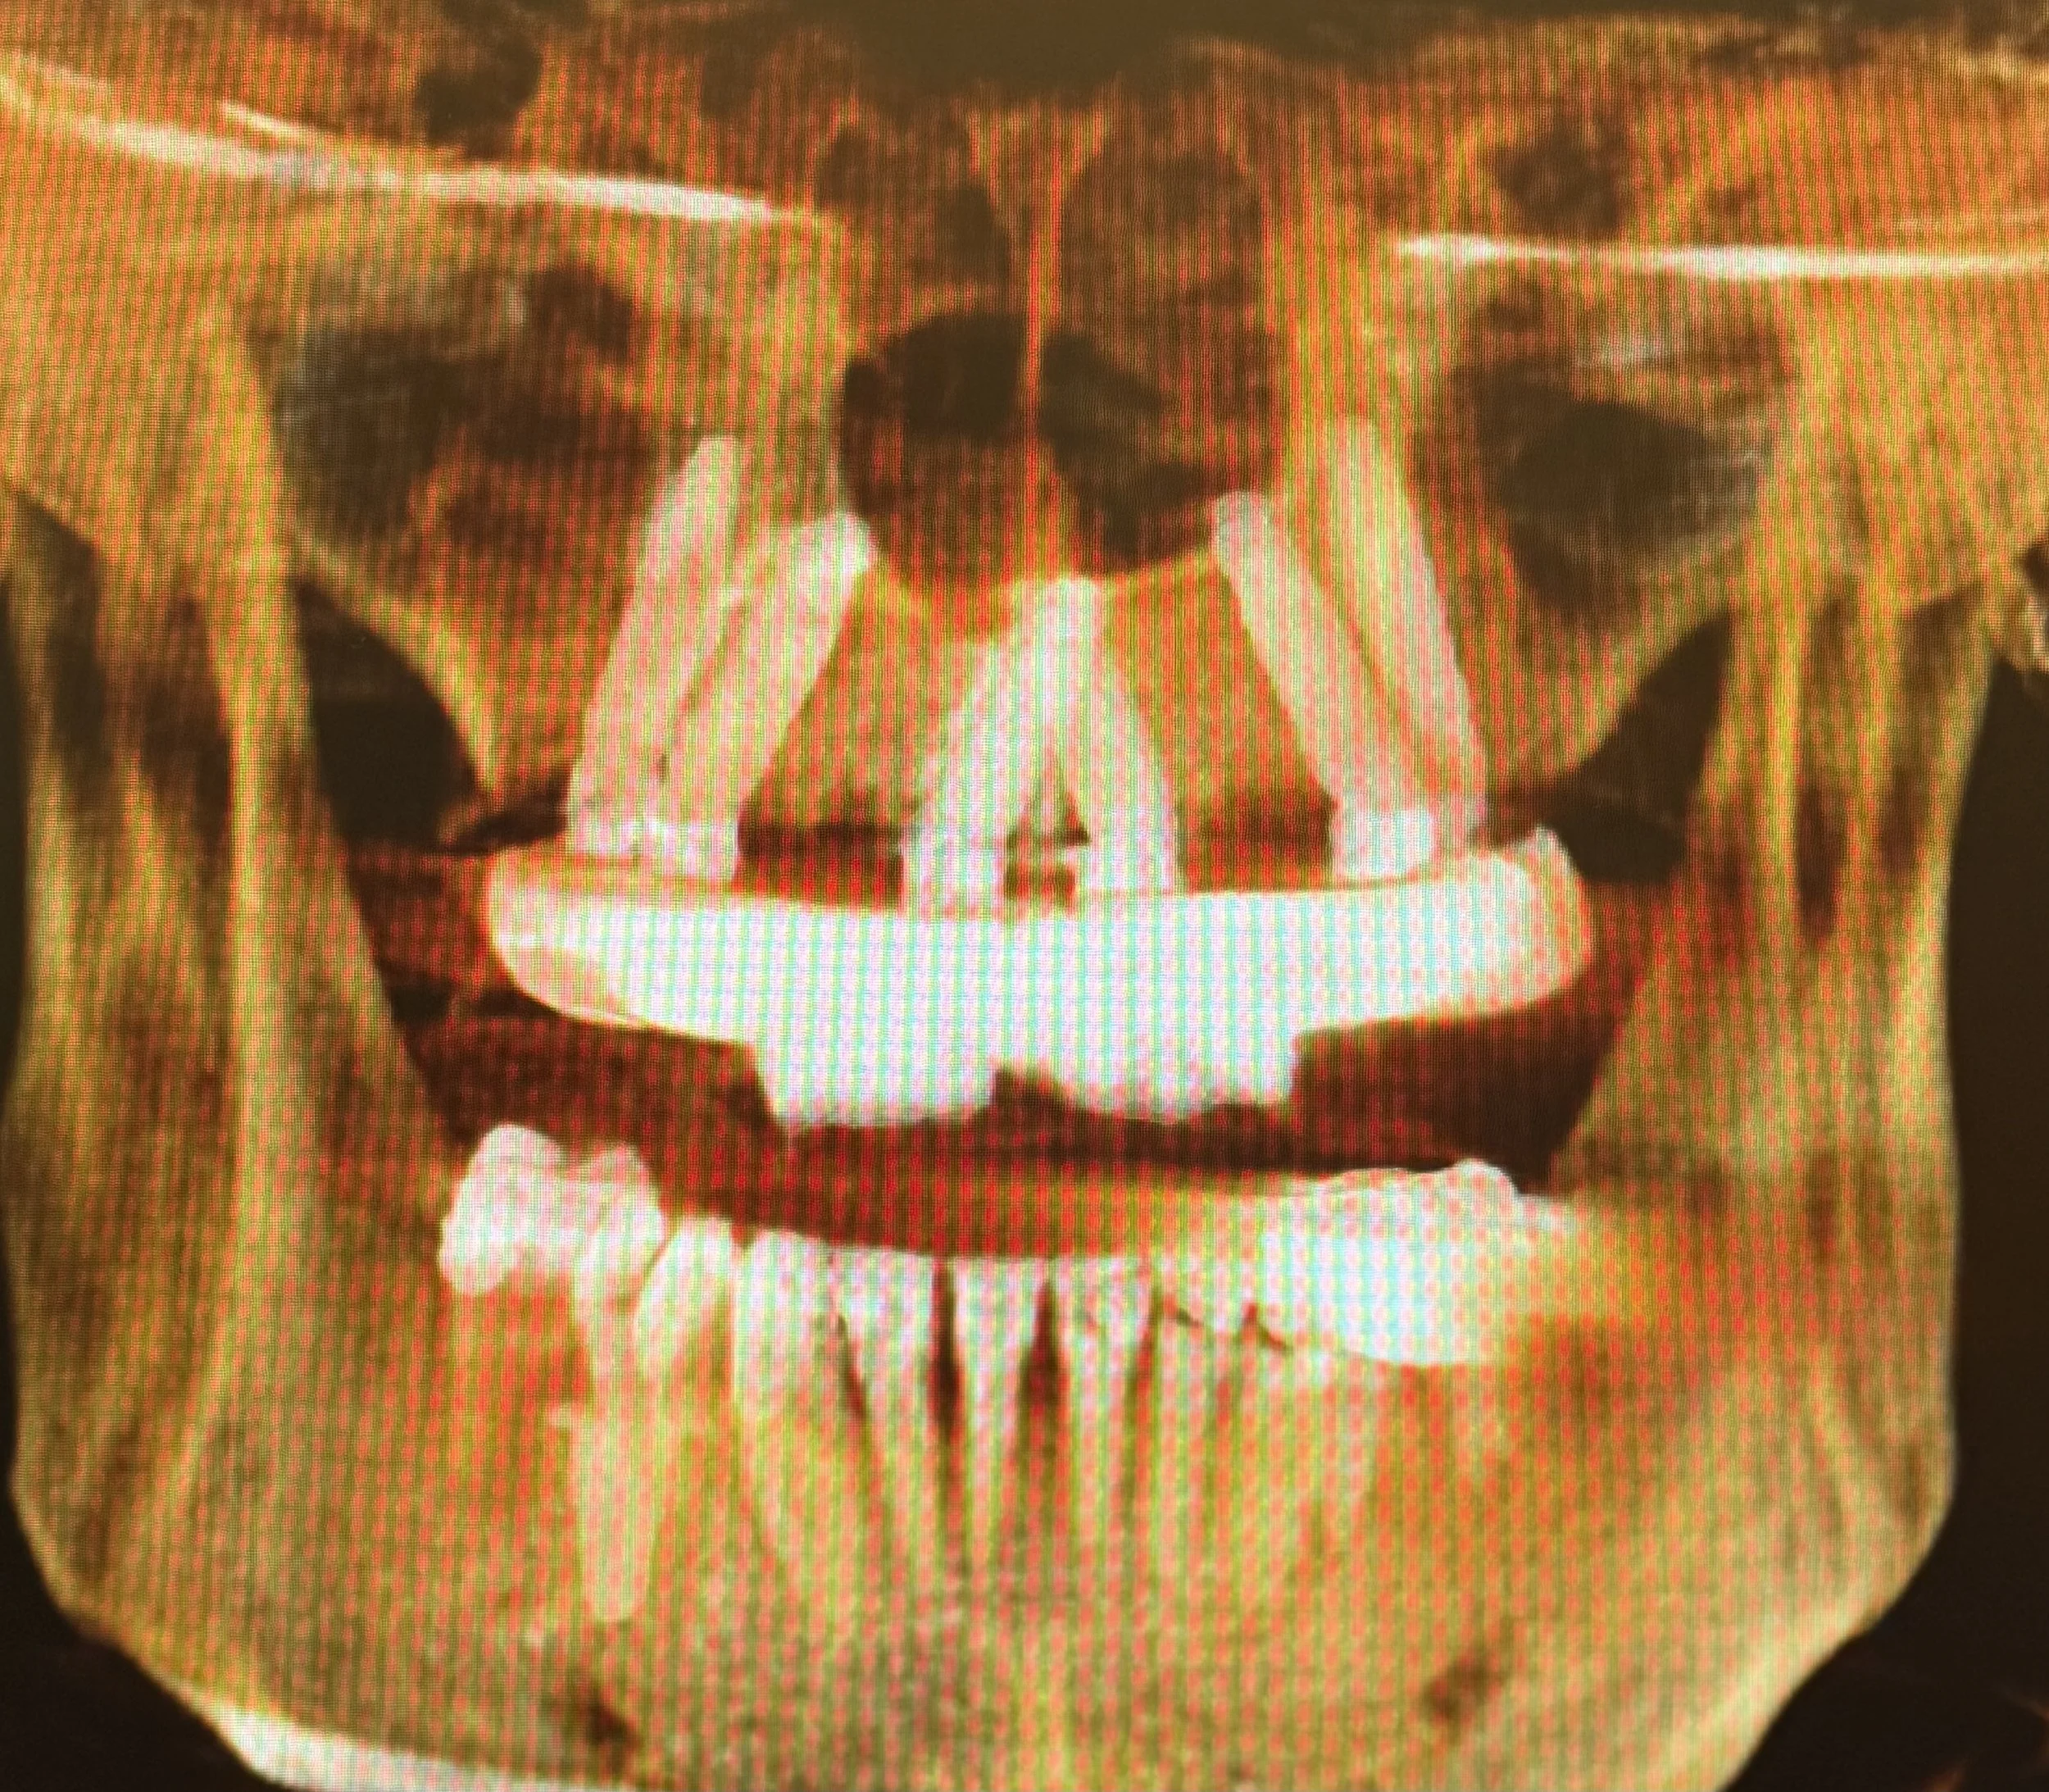

Dr. Damons Cases